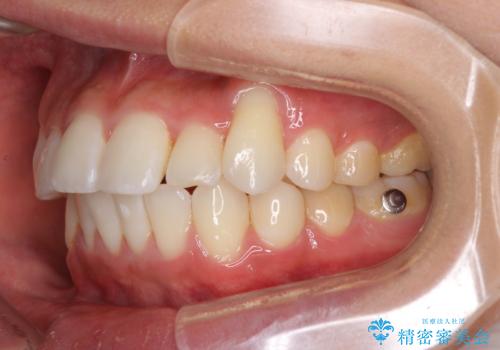

八重歯と奥歯のクロスバイト 上顎骨を拡大してインビザラインで矯正

- 八重歯を気にして来院された患者様です。

八重歯が著しいため、抜歯矯正も視野に入れて検討しましたが、臼歯の咬合関係は正常に近かったので、非抜歯矯正で進める方針としました。

上顎骨の幅が狭く、奥歯がクロスバイトとなっていたため、急速拡大装置を用いて上顎骨を側方拡大し、八重歯を収めるスペースを獲得しつつクロスバイトを改善することとしました。

上顎骨を思い通りに拡大できたため、当初の計画通りに非抜歯矯正で仕上げることができました。